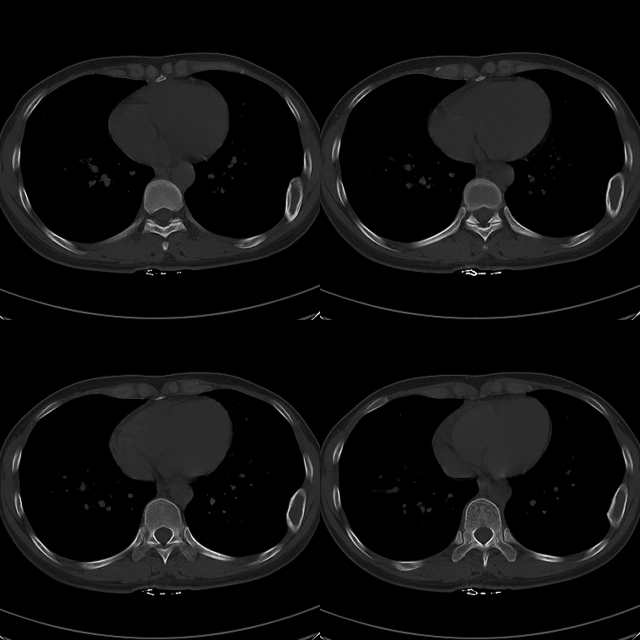

标题: CT19623:F40y,肋骨改变。

40岁女性,双侧胸部疼痛,以左侧为明显1+年。余无明显异常。

左侧肋骨单发膨胀性病变,皮质连续,病史较长,首先考虑良性病变:骨纤可能性大。

左侧肋骨骨纤维异常增殖症可能。

考虑左侧肋骨骨纤维异常增殖症可能。